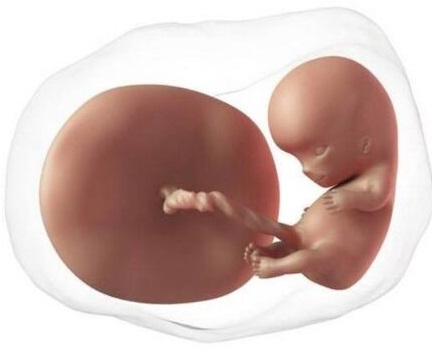

Ahora el embrión está dentro de una bolsa llena de líquido que crecerá durante todo el embarazo. El embrión tiene forma de tubo, todavía no tiene extremidades. Se empiezan a formar lo que serán huesos, músculos, sistema nervioso. El embrión ya tiene corazón que se contrae en forma rítmica, permitiendo enviar glóbulos rojos con oxígeno a todo su pequeño cuerpo. Por supuesto, en esta etapa el corazón es aún un órgano primitivo, pero ya late y no dejará de hacerlo durante toda su vida. El embrión mide entre 1 y 2 mm.

Se empiezan a formar los ojos y aparecen los esbozos de los brazos y las piernas; el corazón consta únicamente de una cámara. En esta semana se inicia la formación de la mayor parte de los órganos del embrión, por lo que es un período crítico en el desarrollo del bebé. El embrión mide entre 2 y 4 mm.

El embrión crece muy rápido, ha pasado de 4 a 14 mm en sólo una semana. Los cambios son impresionantes. En esta etapa inicia la formación de las neuronas y el cerebro ya tiene los dos hemisferios. En la cara aparecen las fosas nasales. El corazón ya tiene dos cámaras (al terminar su formación tendrá cuatro). Inicia la formación de los intestinos los cuales sobresalen a través del cordón umbilical que también está en proceso de formación.